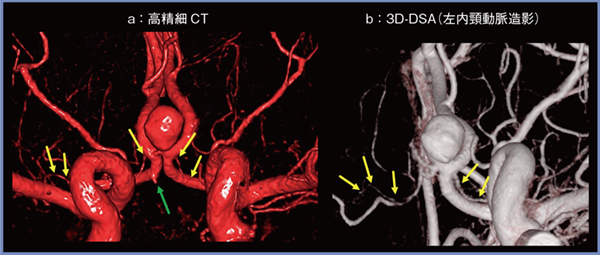

1.穿通枝動脈,小型動脈瘤

穿通枝動脈は脳の重要な箇所を灌流する細い動脈で,脳外科手術では原則的に絶対温存が求められる。図1は前交通動脈瘤の症例である。前大脳動脈から起始するHeubner動脈(図1 ↓)は直径約0.8mmほどの穿通枝動脈であるが,DLRを用いた高精細CT(a)では,3D-DSA(b)と同様に描出できていることがわかる。また,DSAの左内頸動脈造影では描出されていない右前大脳動脈の小型動脈瘤(図1 a↑)も,高精細CTでは1回の撮影で明瞭に描出可能である。

図1 前交通動脈瘤